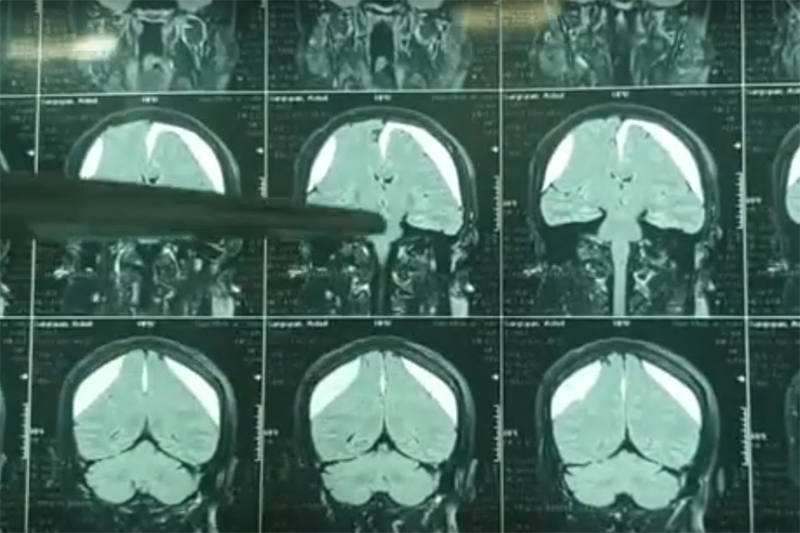

Служба осуществляет диагностику и лечение острых и хронических нарушений мозгового кровообращения, различных центральных и периферических заболеваний нервной системы воспалительного, аутоиммунного, посттравматического генеза, двигательных нарушений, а также минимально инвазивные оперативные вмешательства при различных патологиях головного и спинного мозга.